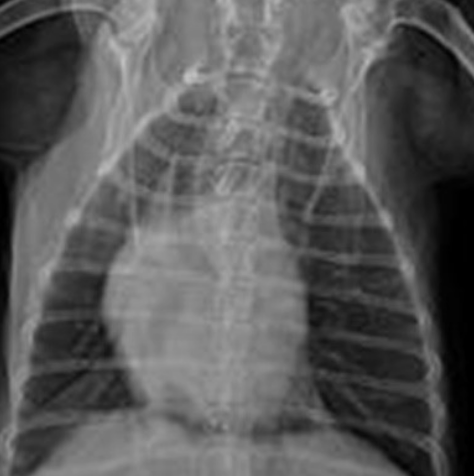

심장병이 기침을 유발하는 이유는 심장병으로 심장이 점점 커져서

기도를 눌러서 기침을 하게 되는데 문제는 기침을 할 정도면

심장병이 많이 진행된 상태가 많아서 빨리 치료를 받아야 하고 요새는

심장이 많이 커지기 전부터 커지지 않도록 관리하는 것인데

기침을 유발할 정도의 심장병이라면 3단계 이상이라 빨리 치료를 받아야 한다고 합니다.